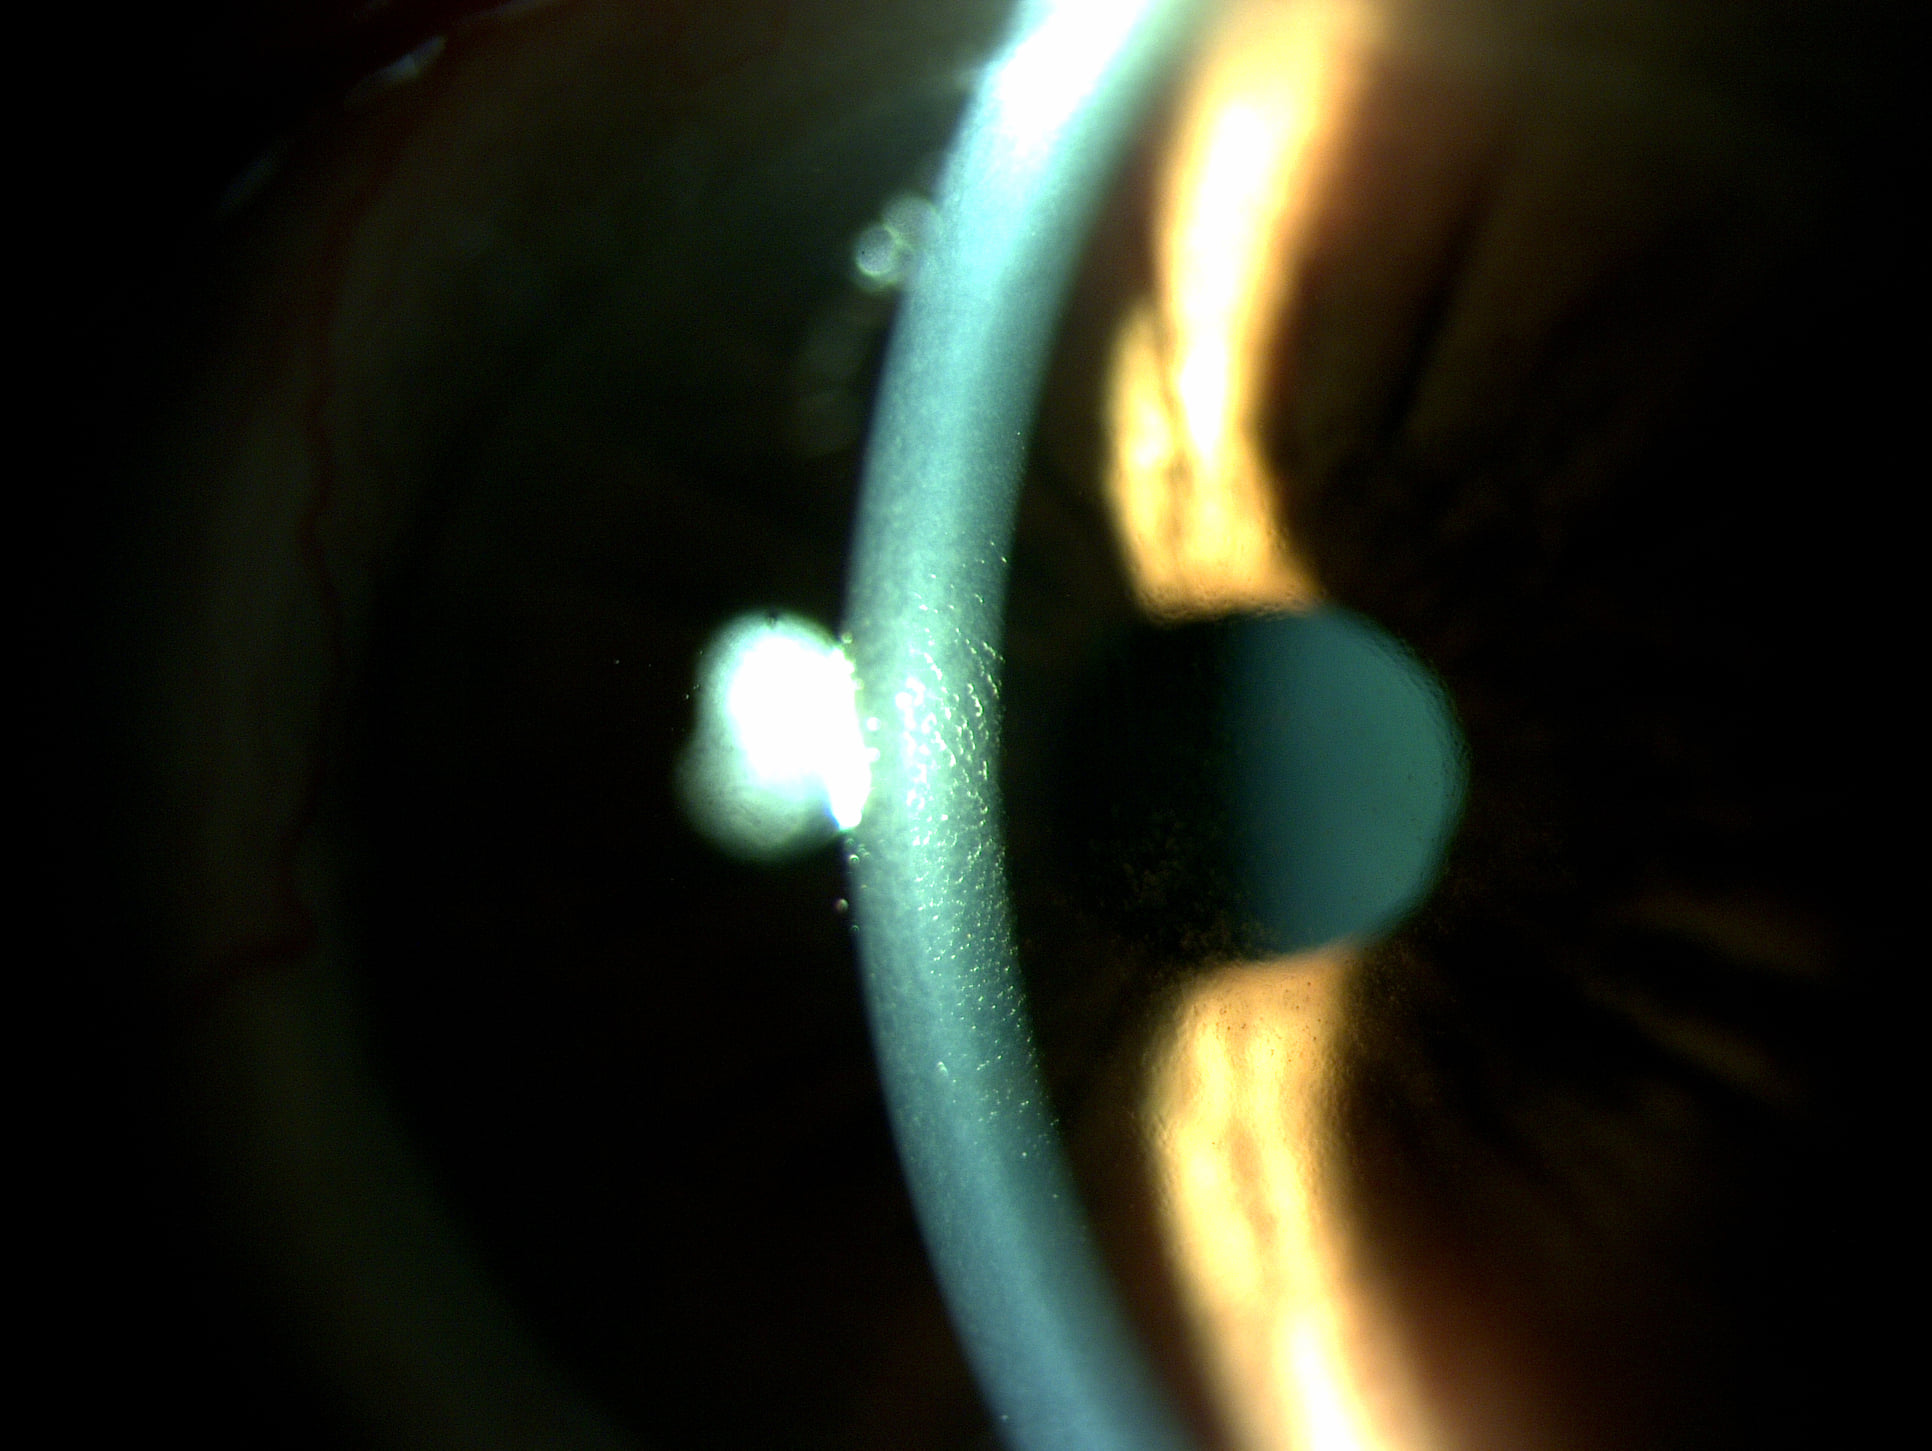

Mai jos, fotografii ale mai multor pacienti de-ai nostri cu Corneea Guttatta în faze medii, sau chiar avansate, la care am efectuat doar operația de cataractă, în urma căreia corneea a „supraviețuit” cu brio și nu a mai fost nevoie – cel puțin până acum – de un trasplant de cornee.